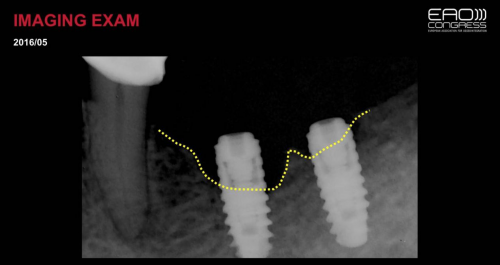

2019年9月,美奥口腔医生代表受邀出席了EAO欧洲骨整合会议,在生物和机械并发症专题论坛,美奥口腔王汉禹院长的病例,成为成功入选的民营机构病例。王院长就《口腔激光在种植体周围早期骨吸收手术性治疗中的作用》课题进行了案例分享和深度剖析,关于种植牙新技术的临床应用,以及目前口腔医学的发展趋势都发表了自己独到的见解。